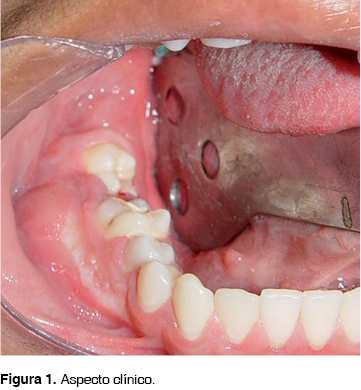

En julio del 2004 se presentó a la Consulta Externa del Hospital Juárez de México un adolescente del sexo masculino de 14 años de edad, con aumento de volumen mandibular del lado derecho, aparentemente de 7 meses de evolución, presentando ligera sintomatología dolorosa a la presión y sin antecedentes previos de relevancia para su padecimiento. La lesión se extendía del segundo premolar a zona del tercer molar derecho, produciendo expansión vestibular, con desplazamiento y movilidad del primero y segundo molar ipsilateral (Figura 1). La radiografía panorámica mostró una lesión radiolúcida unilocular que abarcaba primer y segundo molar derechos con íntima relación al tercer molar, bordes bien delimitados, de dimensiones aproximadas de 30 x 20 mm, produciendo desplazamiento de los órganos dentales involucrados (Figura 2). La TAC simple mostró una lesión que producía adelgazamiento y expansión cortical vestibular y lingual conservando el borde mandibular (Figura 3).